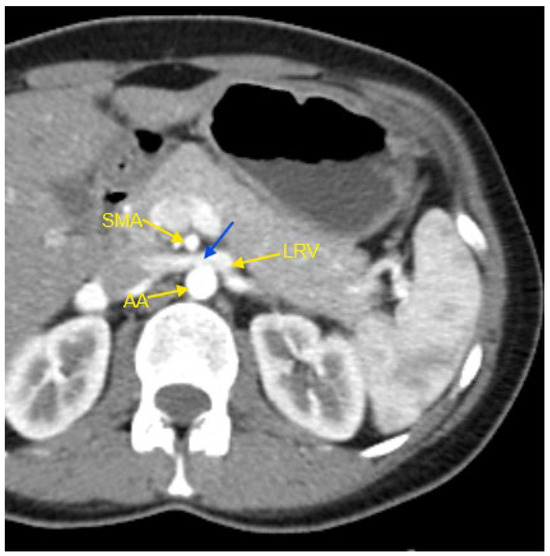

A variety of abnormalities in the renal vasculature were identified, with unilateral accessory renal arteries being the most frequent finding in both groups. However, this abnormality had a significantly higher prevalence in the resistant HTN group. Other more common findings included bilateral accessory renal arteries, the presence of two renal veins in a single kidney, and Nutcracker syndrome. The classic form of this syndrome refers to the compression of the left renal vein between the superior mesenteric artery and the abdominal aorta [18]. In our study, four patients presented with this form of Nutcracker syndrome, while one patient—a 28-year-old male—was diagnosed with the rarer right-sided Nutcracker syndrome.

Figure 1, Figure 2, Figure 3, Figure 4 and Figure 5 show examples of some renal vascular abnormalities we identified in our study population.

Figure 1. Contrast-enhanced CT imaging of a 44-year-old female patient with high blood pressure refractory to treatment, revealed characteristic findings consistent with classic Nutcracker syndrome. In the presented image, the abdominal aorta, the superior mesenteric artery, and the left renal vein are indicated by yellow arrows. The compressed segment of the left renal vein is highlighted by a blue arrow. AA—abdominal aorta; CT—computed tomography; LRV—left renal vein; SMA—superior mesenteric artery.